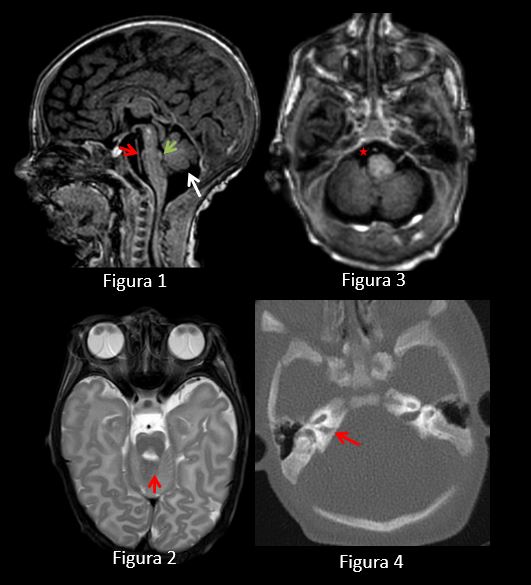

RM realizada sin contraste y con técnica de cojín. TC sin contraste y sin anestesia.

Figura 1: RM secuencia sagital T1. Aplanamiento ventral de la protuberancia (flecha roja) y protrusión del tegmento pontino (“tegmental cap”) hacia el cuarto ventrículo (flecha verde). Vermis hipoplásico con alteración de la foliación (flecha blanca).

Figura 2: RM secuencia axial T2. Anomalía de pedúnculos cerebelosos superiores (“molar tooth”) (flecha roja).

Figura 3: RM secuencia axial T1. No se identifican pares craneales derechos VII y VIII (estrella roja).

Figura 4: TC axial. Asimetría de CAIs con hipoplasia del derecho (flecha roja) así como del conducto del facial.